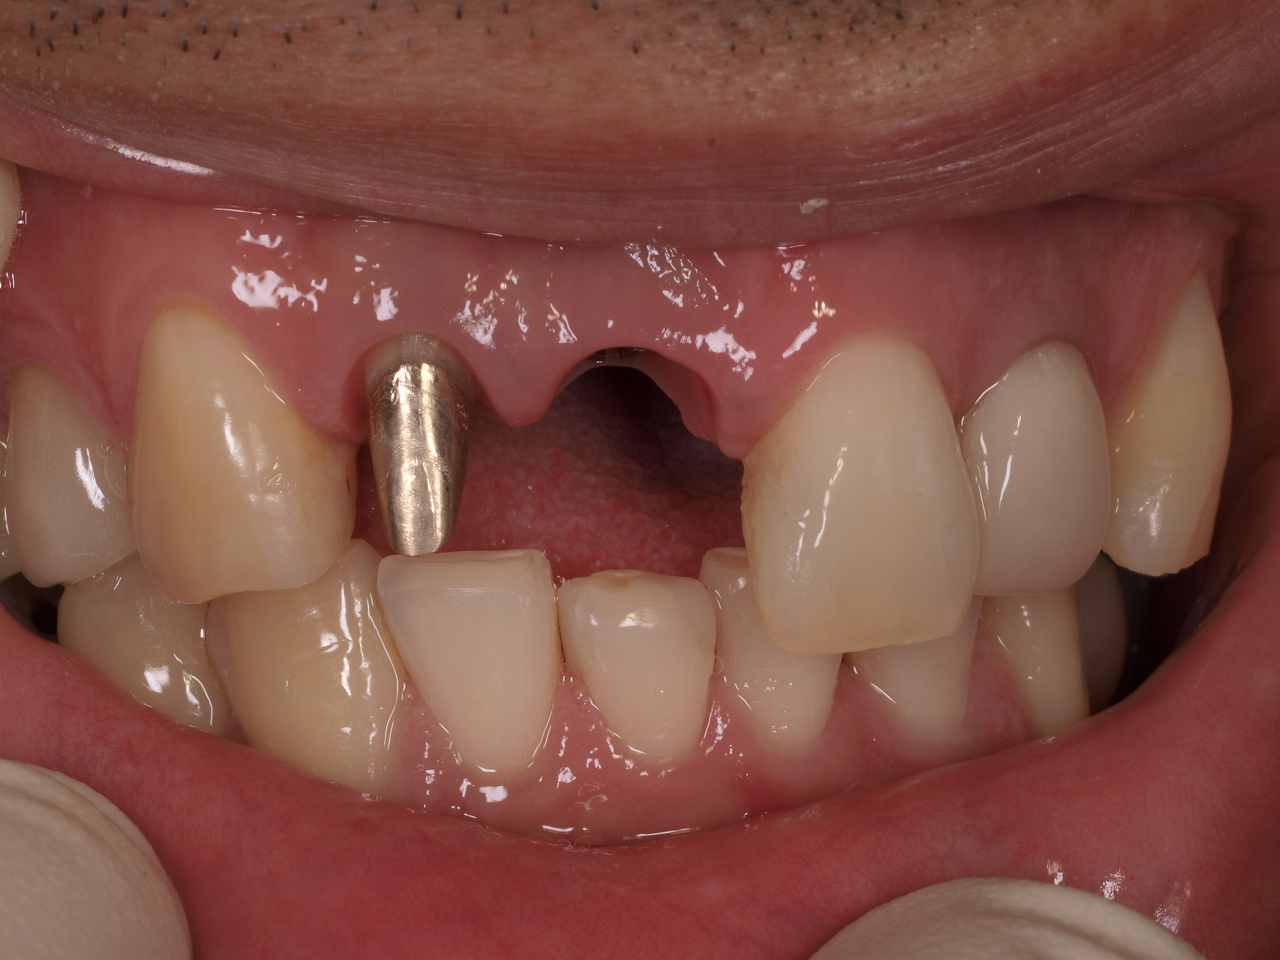

状態のよい時期に抜歯即時インプラント埋入を行うことによって前歯部のインプラントを天然市と変わらないようにきれいに仕上げる これに尽きるのが技術かと思います

状態のよい時期に抜歯即時インプラント埋入を行うことによって前歯部のインプラントを天然市と変わらないようにきれいに仕上げる これに尽きるのが技術かと思います

ブラックトライアングルは認めなく、抜歯したにもも関わらず

大きな歯肉退縮もありません

すべて単冠で仕上げています

アバットメントをジルコニアアバットメントで仕上げればもう少し

メタル色を消せたかもしれません

ですがきれいに仕上がったと患者さんからも満足していただきました